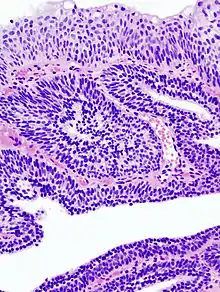

Photomicrographie d'un papillome malpighien sur une langue. Coloration à l'hématoxyline et à l'éosine.

- Papillome urothélial : lésion urothéliale composée d'axes conjonctifs bordés par des cellules urothéliales, rappelant la structure des "papilles". Il peut être exophytique ou inversé, dans ce dernier cas les cellules épithéliales proliférantes s'invaginent dans le stroma sous-jacent[1].

- Papillome malpighien : composé d'axes conjonctifs bordés par des cellules malpighiennes, rappelant la structure des « papilles ». Ils peuvent former un relief à la surface ou s'invaginer dans la muqueuse (papillome inversé).